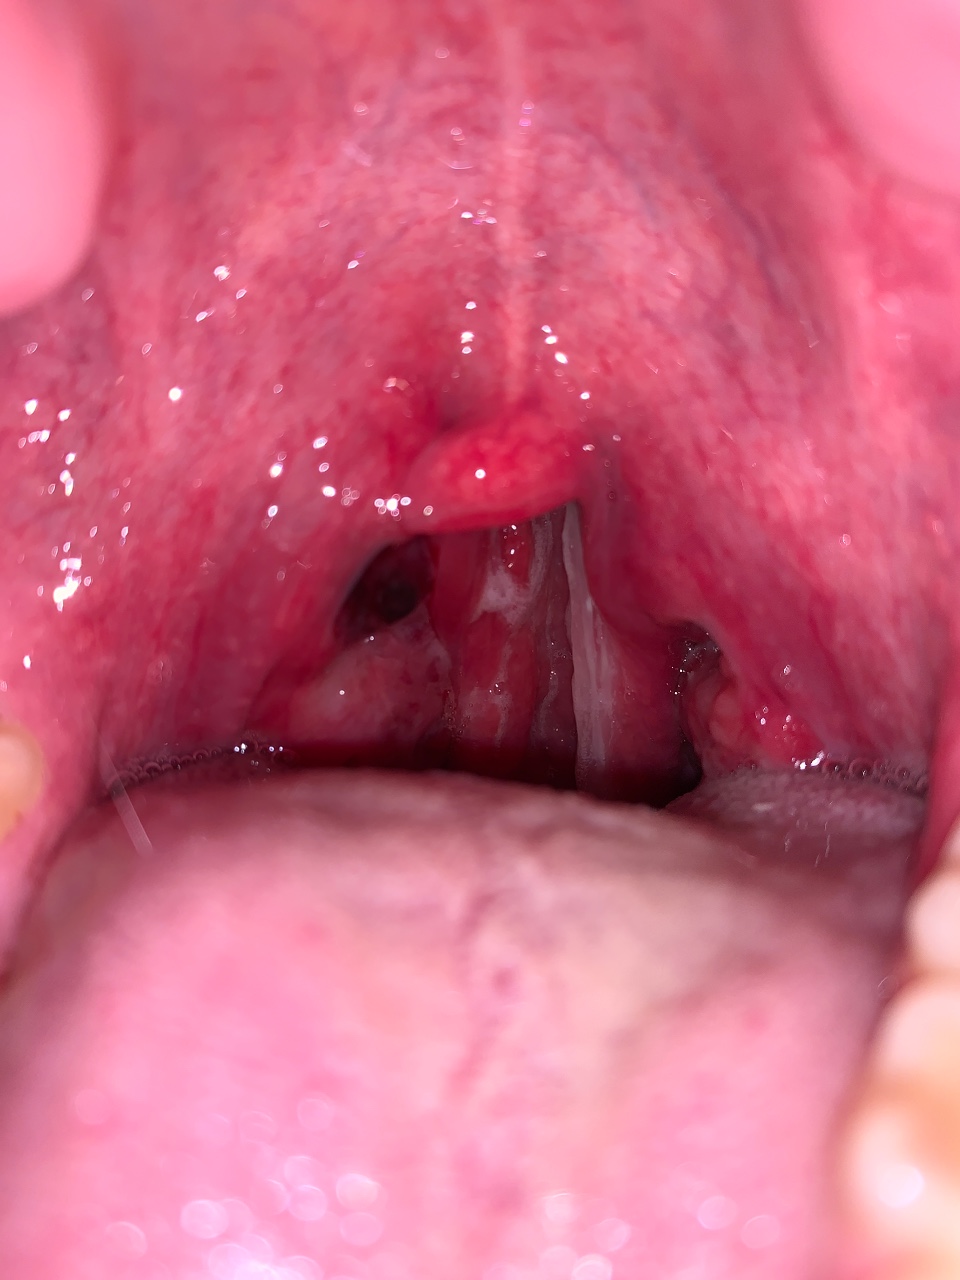

Чёрная миндалина

Здравствуйте, вчера сходил на тренировку и потел как будто в душ сходил, у меня это почти всегда, но вчера особенно. Ещё ходил в сауну на 10 минут, потом дошёл до дома и почувствовал легкое неприятное ощущение в горле. В итоге долго не мог заснуть, боль в горле усиливалась, каждый час просыпался, а утром уже понял что я вообще почти глотать не могу из-за боли, причём больше в правой части горла. Решил посвятить фанариотом на гланды и посмотреть, а они в ужасном состоянии. Миндалина справа вообще какого-то чёрного цвета…Горло моё уязвимое место и миндалины бывает набухали, но тут прям чёрного цвета и в слюне немного есть крови. Кашля нет, с температурой непонятно, нет градусника, нос немного заложен и пи глотании боль слегка отдаёт в правок ухо со стороны чёрной миндалины. Лимфоузлы не набухли.